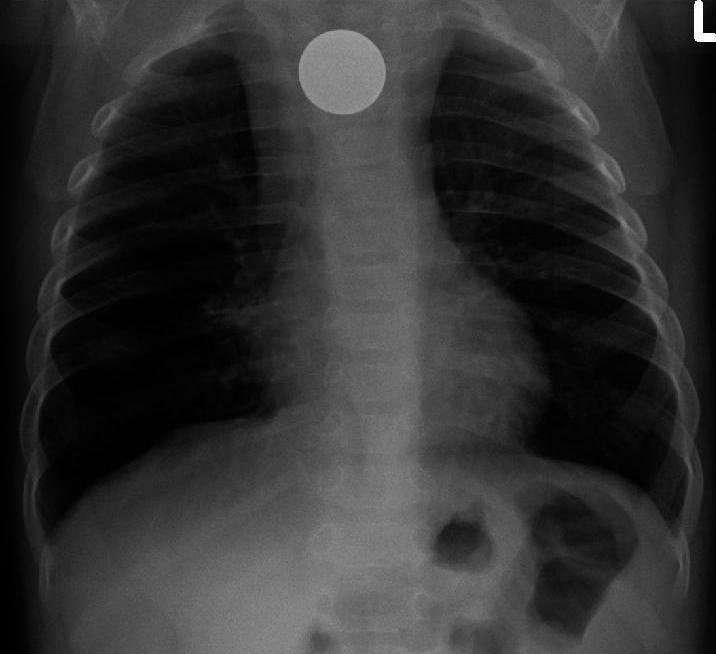

A child of 2 years 8 months was admitted to the Department of Pediatric Surgery of the Republican Research Centre of Emergency Medicine. Complaints at admission were difficulty in swallowing thick food, fever, lethargy, decreased appetite and frequent colds. From the anamnesis it became known that during the last four months, while eating, the child vomited up to 2-3 times a week. The child was consulted by a pediatrician, ENT doctor and neurologist. No pathology was revealed. Then the child was referred to a pediatric surgeon and a plain chest X-ray was performed. Chest X-ray revealed FB of the upper parts of the GI tract. An attempt of the FB endoscopic removal was made, but unsuccessfully. Then the patient was referred to our Centre.At admission the child was passive. Cardiopulmonary activity was satisfactory. There was no subcutaneous emphysema in the neck and chest area. The abdomen was soft, regular, not swollen and accessible on palpation, painless. There were no symptoms of peritoneal irritation. Physiological functions were normal. At contrast esophagography (trazograph 76%), estvasation was not observed. The FB of the cervical esophagus was determined (Fig. 1). | Figure 1. Plain radiography in direct projection: at the Th 2-Th4 level, a round-shaped radiopaque FB with a diameter of 2 cm is determined |